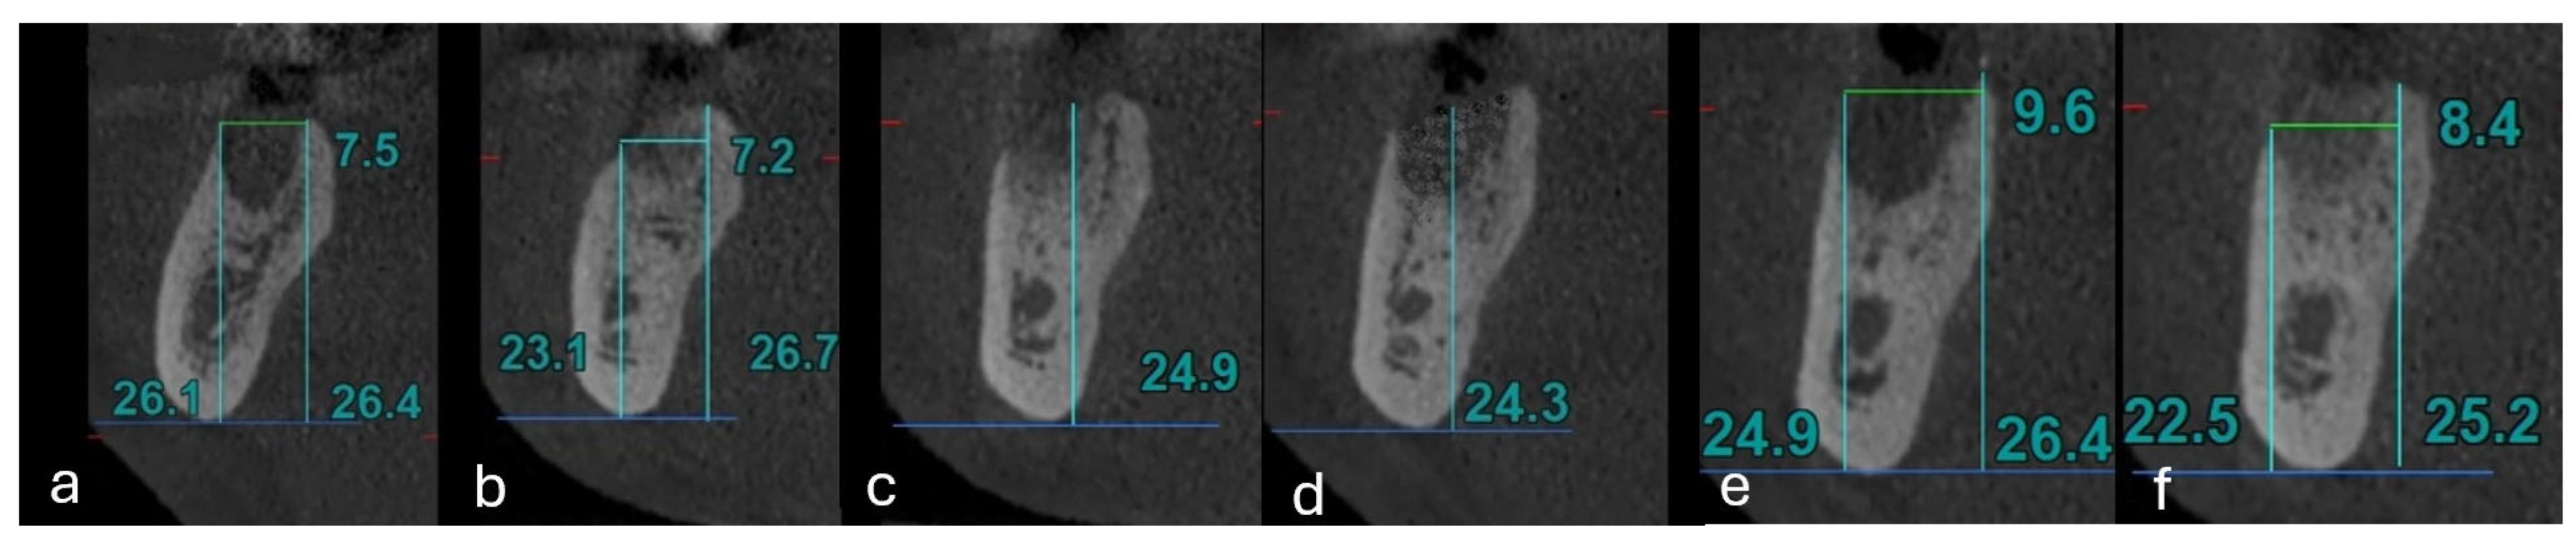

| Dimension (mm) | On the Day of the Procedure | 4 Months After the Procedure | Result of the Test |

| High septum—with laser | 24.7 (23.4–27.9) | 24.2 (22.0–26.8) | p = 0.001 |

| High septum—no laser | 23.0 (20.7–26.1) | 20.2 (20.0–24.8) | p <0.001 |

| Result of the test | p = 0.206 | p = 0.125 | × |

| High mesial buccal—with laser | 26.2 (24.4–29.7) | 25.8 (23.7–28.6) | p = 0.001 |

| High mesial buccal—no laser | 24.6 (22.8–27.6) | 22.5 (20.8–26.3) | p = 0.001 |

| Result of the test | p = 0.245 | p = 0.056 | × |

| High mesial lingual—with laser | 27.9 (24.9–30.3) | 25.8 (23.8–28.3) | p = 0.001 |

| High mesial lingual—no laser | 23.7 (23.0–28.8) | 21.9 (21.0–26.4) | p = 0.001 |

| Result of the test | p = 0.184 | p = 0.125 | × |

| Width mesial root—with laser | 8.8 (8.1–9.4) | 8.1 (7.8–8.7) | p = 0.001 |

| Width mesial root—no laser | 9.6 (7.5–10.5) | 8.7 (7.3–10.2) | p = 0.001 |

| Result of the test | p = 0.395 | p = 0.648 | × |

| High distal buccal—with laser | 27.0 (24.0–28.5) | 25.4 (23.2–27.3) | p = 0.001 |

| High distal buccal—no laser | 23.7 (22.0–25.5) | 21.3 (20.1–25.5) | p = 0.001 |

| Result of the test | p = 0.081 | p = 0.051 | × |

| High distal lingual—with laser | 26.1 (23.4–27.9) | 25.4 (22.8–27.6) | p = 0.001 |

| High distal lingual—no laser | 23.7 (21.3–27.2) | 21.7 (20.2–24.9) | p = 0.001 |

| Result of the test | p = 0.237 | p = 0.046 | × |

| Width distal lingual—with laser | 8.4 (8.1–9.6) | 8.1 (7.5–8.7) | p = 0.001 |

| Width distal lingual—no laser | 9.0 (7.8–10.7) | 8.7 (7.5–9.9) | p = 0.001 |

| Result of the test | p = 0.468 | p = 0.384 | × |